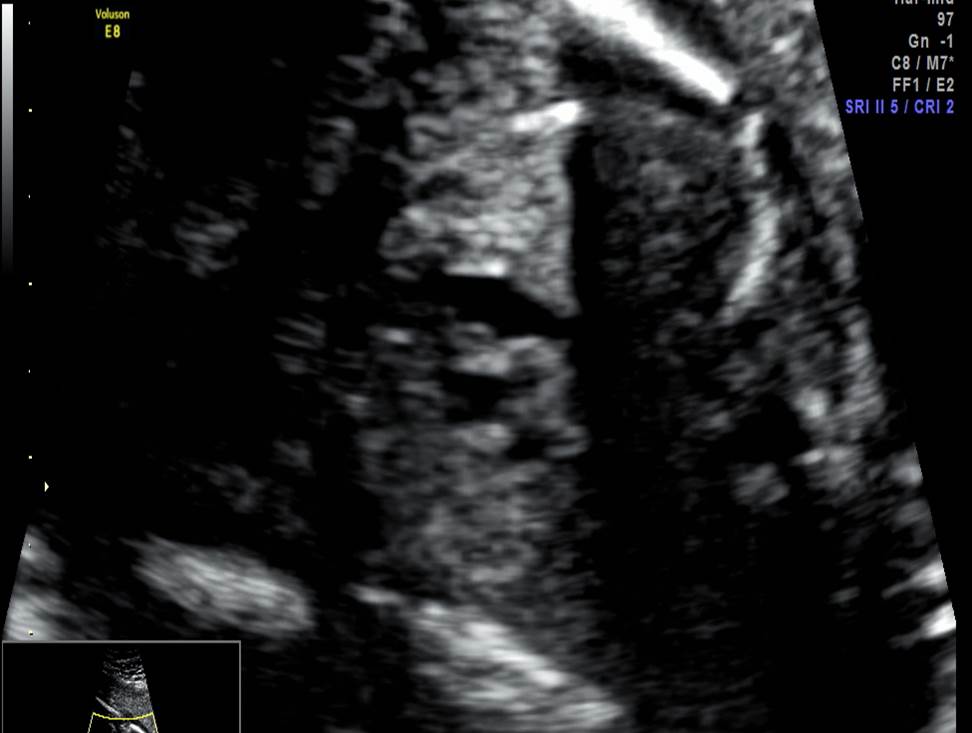

Вопрос 2

- Проанализируйте изображения плода в 22 недели, есть ли у него какие-либо маркеры хромосомной патологии?

- Необходимо ли рекомендовать инвазивную диагностику? Пациентке 30 лет, в 1 триместре комбинированный риск по трисомии 21 — 1:1200